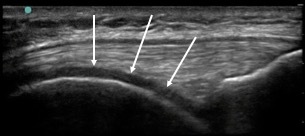

Knee Anterior Trochlear Cartilage 1 Image